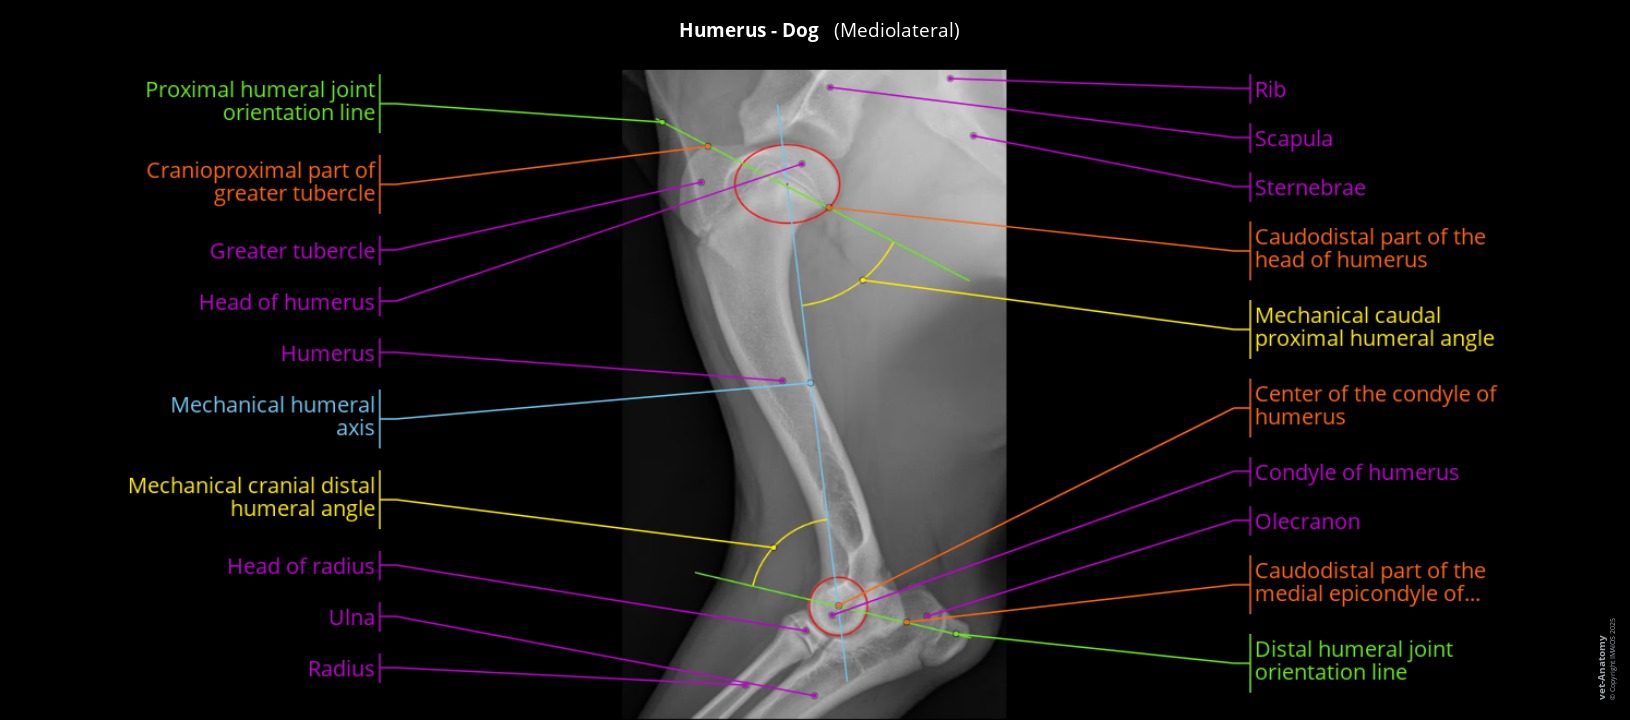

Labelled radiograph of a dog's humerus and elbow

Labeled mediolateral radiograph of a dog’s humerus showing the angles of the scapulohumeral joint and the elbow.